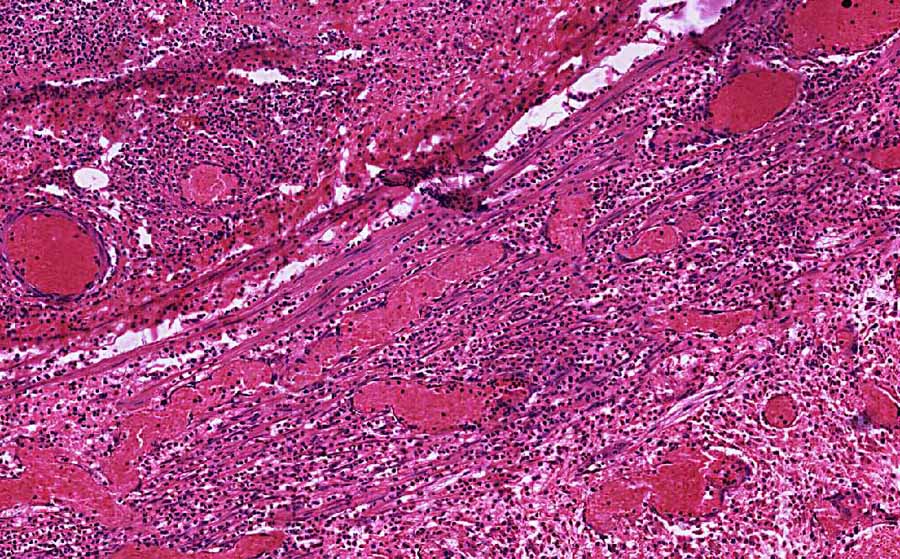

Hematoxylin & eosin

Area 2: The lumen of the appendiceal wall is necrotic and contains substantial viable or non-viable neutrophils. Congested blood vessels are also present.